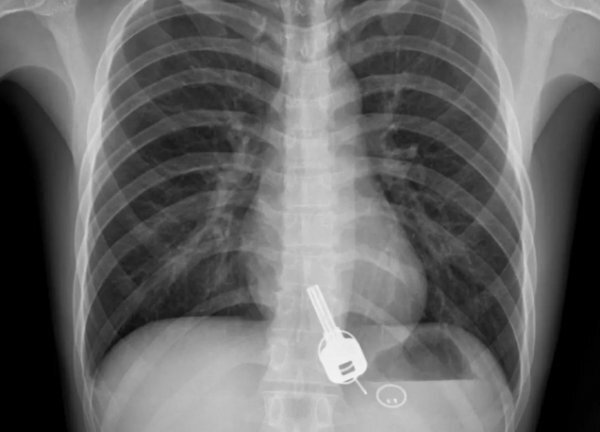

Китаец так напился, что неосознанно проглотил ключ от дома

Об истинной судьбе своих ключей мужчина узнал лишь на следующий день, когда после пробуждения он испытал сильную боль в груди и вынужден был обратиться в местную больницу. Сотрудники клиники Дунгуань были шокированы результатом рентгена торса Чанга, ведь на снимке они увидели ключ с брелоком, застрявший в пищеводе пациента.

Как ключ оказался в его теле китаец ответить не смог, ведь находка докторов его удивила не меньше, чем их. Мужчина признался, что до того, как увидел свой рентгеновский снимок, думал, что потерял ключ, когда напился.